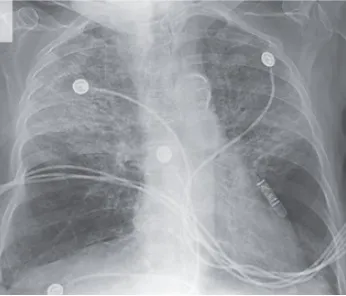

¡Atención al uso prolongado de Nitrofurantoína en ITU recurrente!

¡Atención al uso prolongado de Nitrofurantoína en ITU recurrente!

Siempre debemos prestar atención a los efectos secundarios de los medicamentos más comúnmente utilizados. ¡Echa un vistazo a este caso clínico!